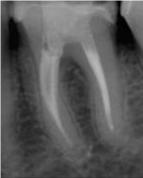

Depois![]() |